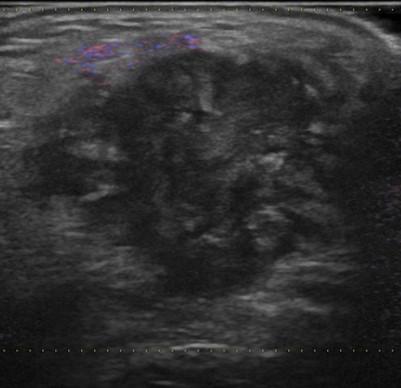

U tuyến nước bọt

» Thông tin: Nam giới – 83 tuổi.

» Lâm sàng: Khối vùng mang tai.

# Ung thư biểu mô tuyến (Adenocarcinoma).